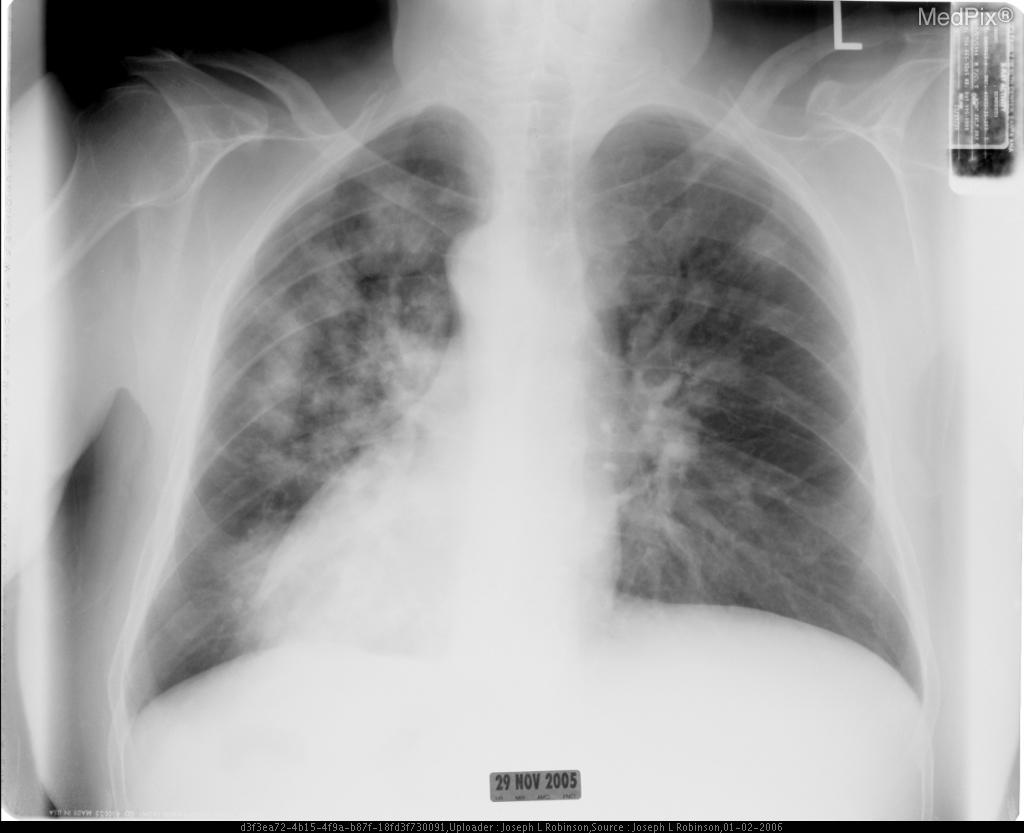

- Pulmonary edema (Figure 2)